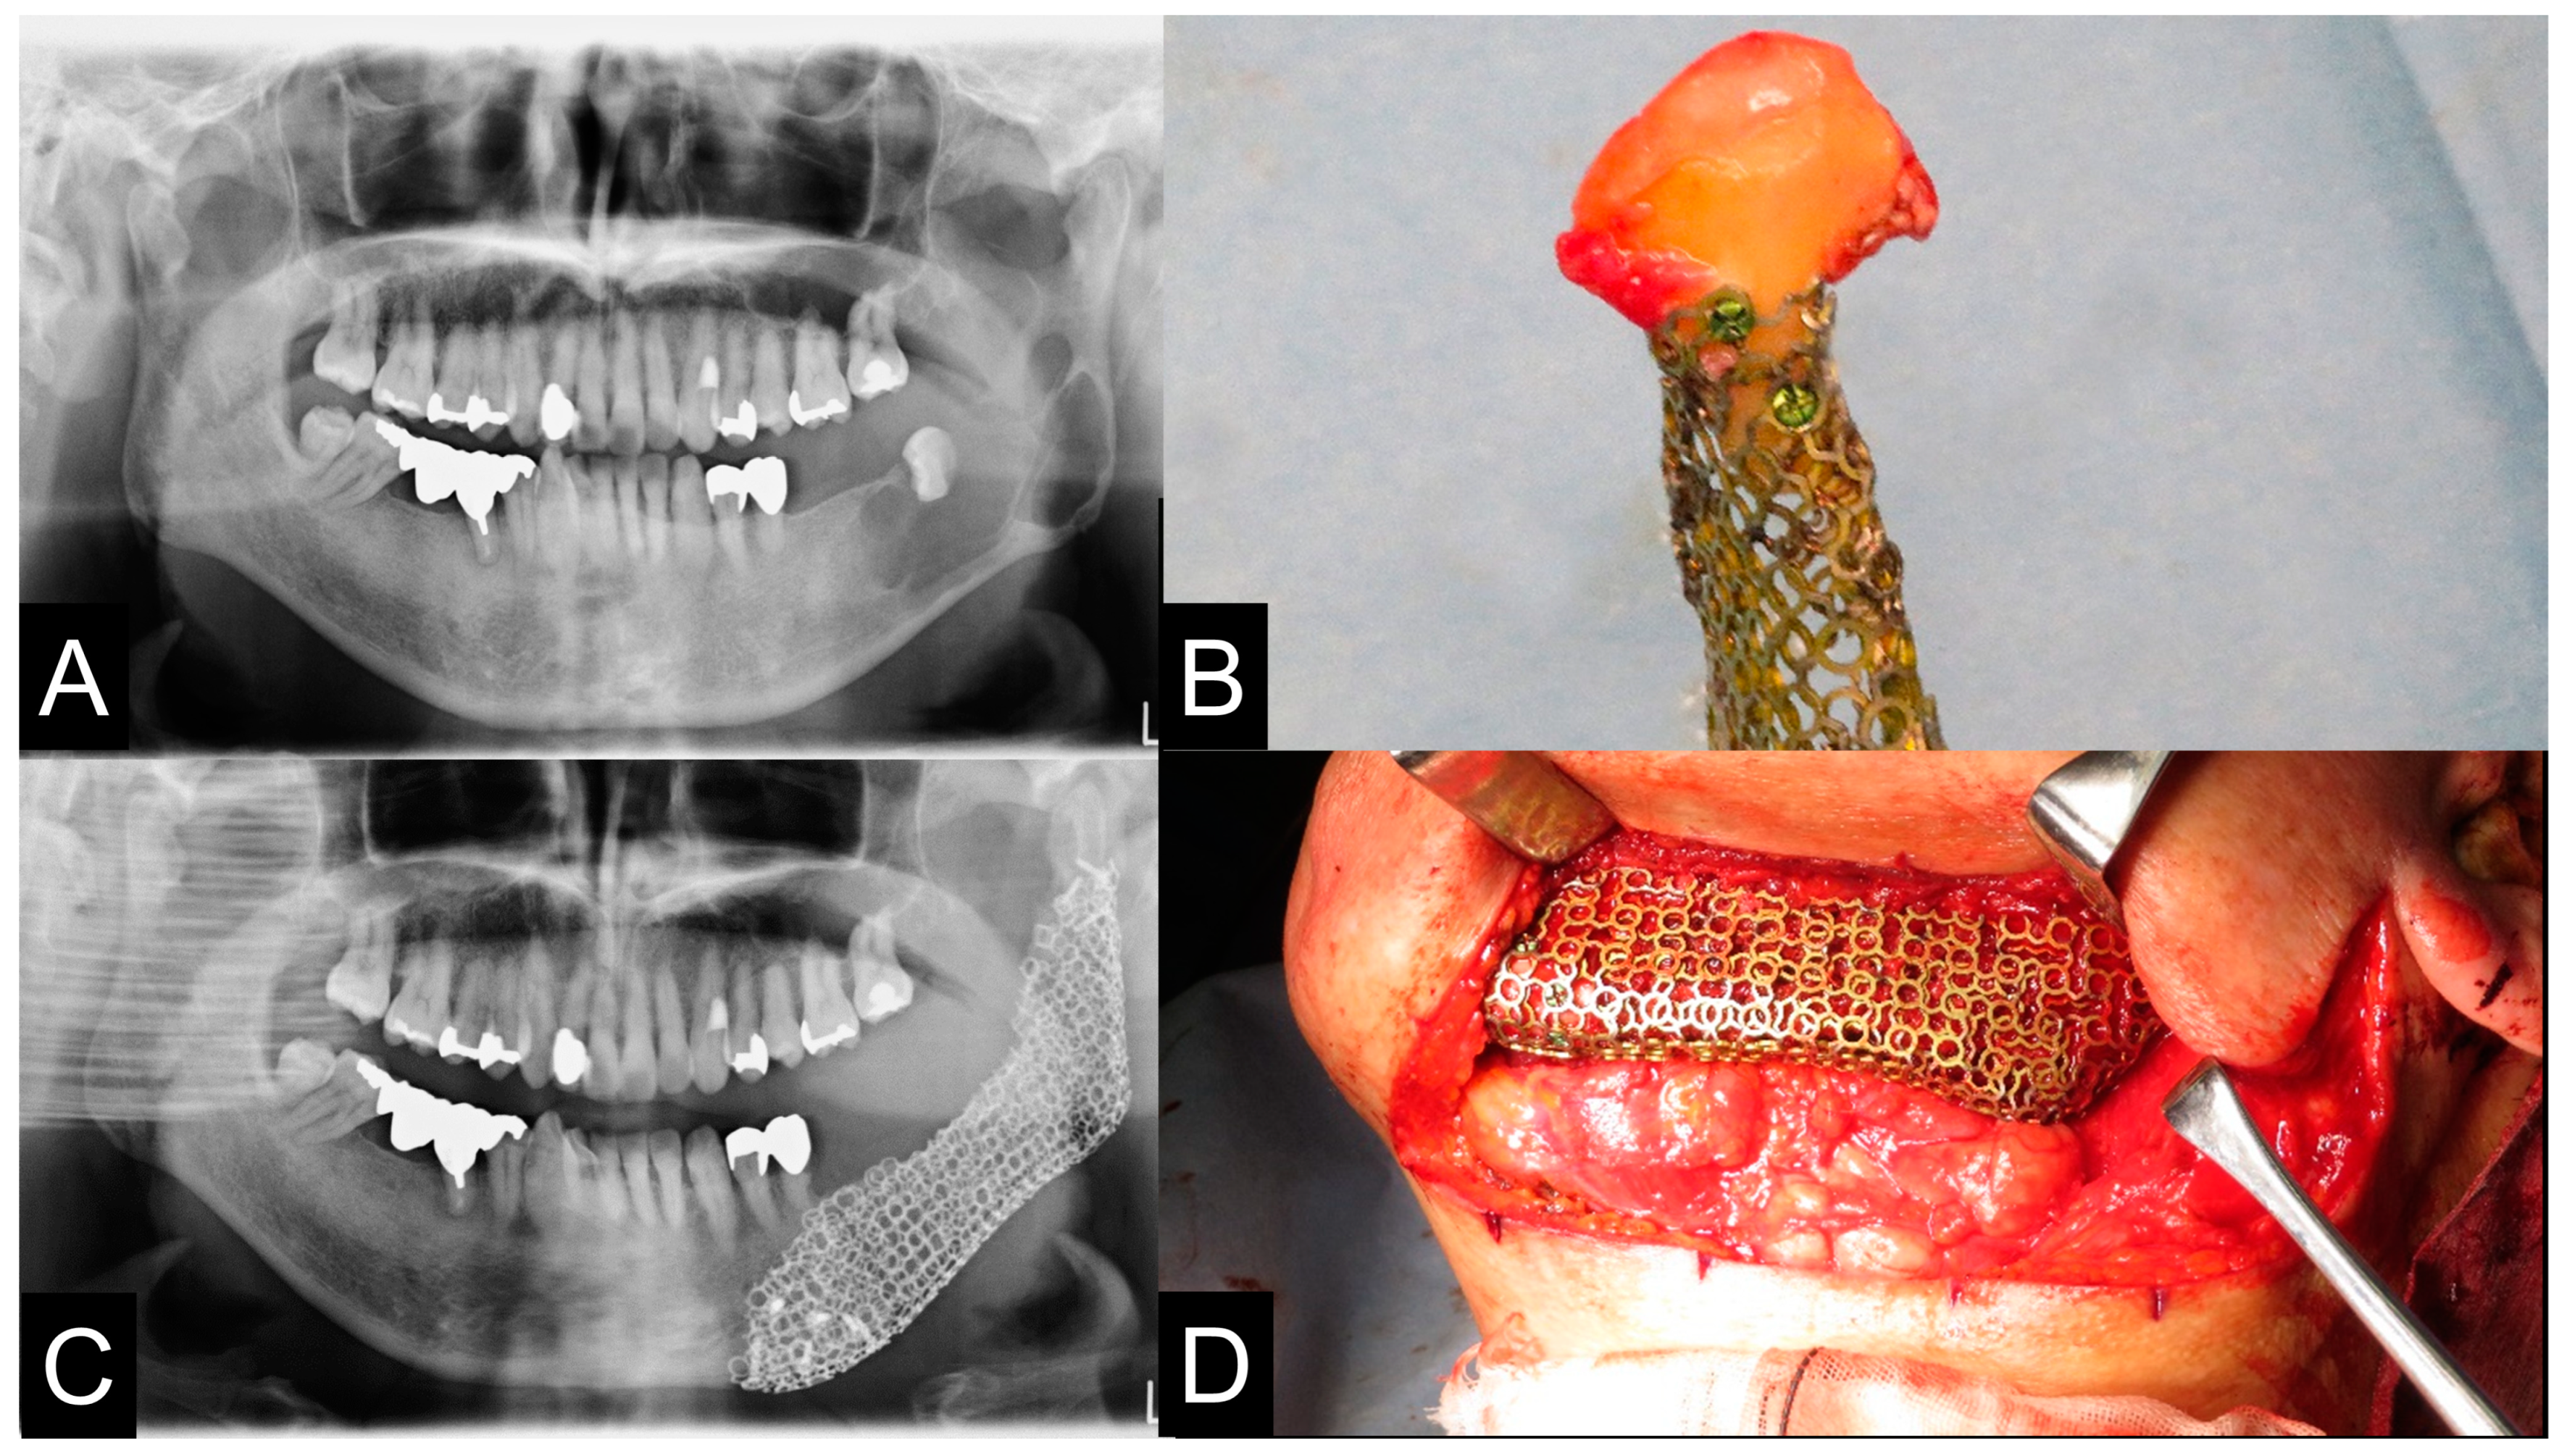

2.5. 3D Printing Model Fabrication and Titanium Mesh Pre-Bending

2.8. Clinical Procedures